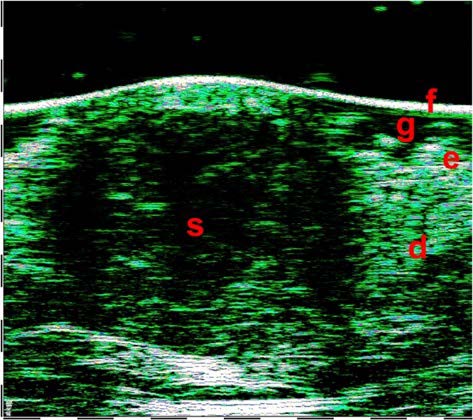

2.9mm depth , 7.1mm width

Οζώδες Βασικοκυτταρικό Καρκίνωμα. Σάρωση με υπέρηχο υψηλής συχνότητα που δείχνει τις διαστάσεις του όγκου και Βιντεοδερματοσκόπηση.

ΒΑΣΙΚΟ ΚΥΤΤΑΡΙΚΟ ΚΑΡΚΙΝΩΜΑ (BCC)

Η βάση της επιτυχημένα επιλεγμένης τακτικής για τη θεραπεία του BCC είναι η σωστή αξιολόγηση της κλινικής του μορφής και της μορφολογίας του. Ο υπέρηχος υψηλής συχνότητας καθιστά δυνατή τη διαφοροποίηση των τύπων BCC: επιφανειακά, οζώδη, σκληροδερμικά και μικροοζώδη.

Τα επιφανειακά BCC στις υπερηχογραφικές σαρώσεις έχουν οριζόντια επιμήκη περιγράμματα με σαφή οριοθέτηση από το υποκείμενο χόριο με υποηχογενή δομή, ενώ τα οζώδη BCC χαρακτηρίζονται από στρογγυλά ή οβάλ περιγράμματα με διάχυτη υπο-ετεροηχογενή δομή και είναι επίσης σαφώς οριοθετημένα από τους περιβάλλοντες ιστούς. Συχνά οι κουκκίδες που μοιάζουν με εγκλείσματα εμφανίζονται στο κέντρο του όγκου και στην περιφέρεια.

1η εικόνα:

ΕΠΙΦΑΝΕΙΑΚΟ BCC

2η εικόνα:

ΟΖΩΔΕΣ BCC

Εικόνα: Οζώδες BCC (Βασικοκυτταρικό Καρκίνωμα).

Υπερηχογράφημα υψηλής συχνότητας με μεγέθη όγκων και βιντεοδερματοσκόπηση.